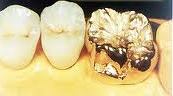

Mão kim loại

Mão răng có thể được làm bằng kim loại, có nhiều loại kim loại được sử dụng, thông thường là hợp kim Ni-Cr, Cr-Co, Titan, hợp kim vàng (Au)

Mão vàng.

+ Ưu điểm: Sửa soạn cùi Răng để bọc mão vàng đơn giản và ít gây biến chứng nhất; vì có rất ít mô Răng bị lấy đi do mài và mô Răng lành mạnh còn lại được bảo tồn tối đa. Không như mão sứ, mão vàng không gây tình trạng mòn mặt nhai các Răng đối diện. Mão vàng cũng dễ gắn khít vào cùi Răng hơn. Vàng là 1 chất hoàn toàn không gây ảnh hưởng có hại nào cho mô nướu.

+ Khuyết điểm: không thẩm mỹ do màu ánh vàng của nó